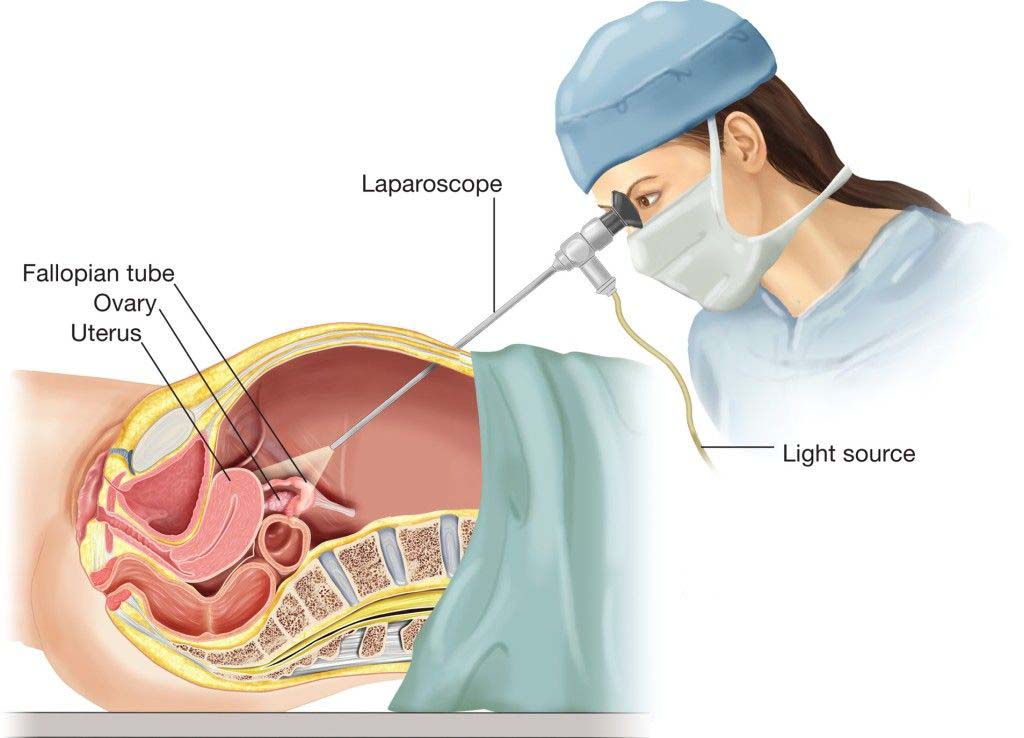

قیمت: 32٬000 تومان - دسته بندی فایل: علوم پزشکیپاورپوینت جراحی لاپاراسکوپی

فروش ویژه پاور پوینت حرفه ای جراحی لاپاراسکوپی با تخفیف استثنایی فقط 54 هزار تومان تعداد اسلاید: 21 اسلاید